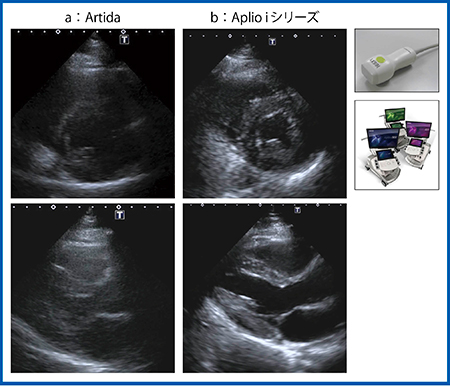

図8は「Artida」とAplio iシリーズの画像比較であるが,新しいプローブでは描出能が飛躍的に向上している。

図8 Artida(a)とAplio iシリーズ(b)の画像比較